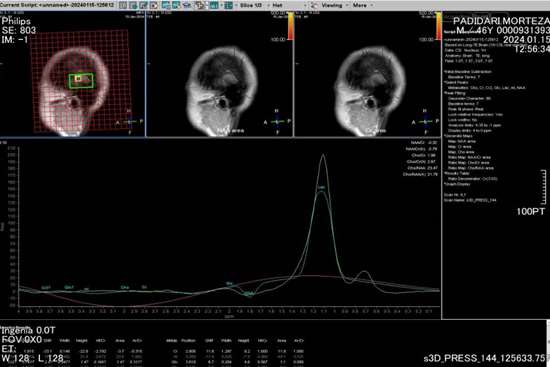

به گزارش پایگاه اطلاع‌رسانی دانشگاه عاوم پزشکی گیلان (وب‌دا)؛ دکتر ظهیر ریحانیان - رئیس مرکز آموزشی و درمانی پورسینا با اعلام این خبر گفت: اولین MRI پیشرفته به صورت DTI و MRS برای بیمار مبتلا به تومور مغزی در مرکز آموزشی و درمانی پورسینا انجام شد.

وی ادامه داد: سکانس‌های فوق برای تشخیص دقیق‌تر ضایعات مغزی و افتراق آن از سایر بیماری‌های مشابه کمک کننده می‌باشد همچنین در این شیوه نقشه برداری دقیق‌تر مغز برای انجام جراحی‌های پیشرفته بسیار حایز اهمیت است.